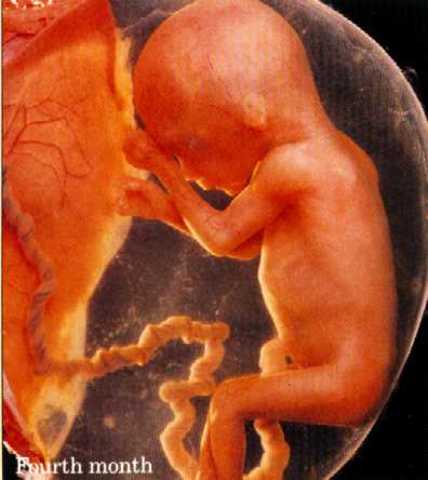

• Second Trimester (fourth month)

Second Trimester (fourth month)

Four to six inches long, weighs four ounces, muscles are developed and fetus moves, skin is pink and transparent, umbilical cord and placenta work properly. Mothers size increases and she enters what is called the "golden trimester" because she experiences little discomfort.